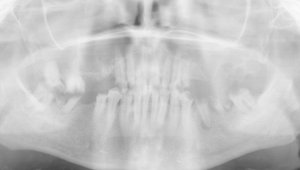

Здравствуйте! Есть ли у меня киста? Если да, то как срочно нужно делать операцию и как она называется?

Какой зуб вы имеете ввиду? Уточните. 18 и 48 зуб необходимо удалить. Далее расскажу после уточнения.